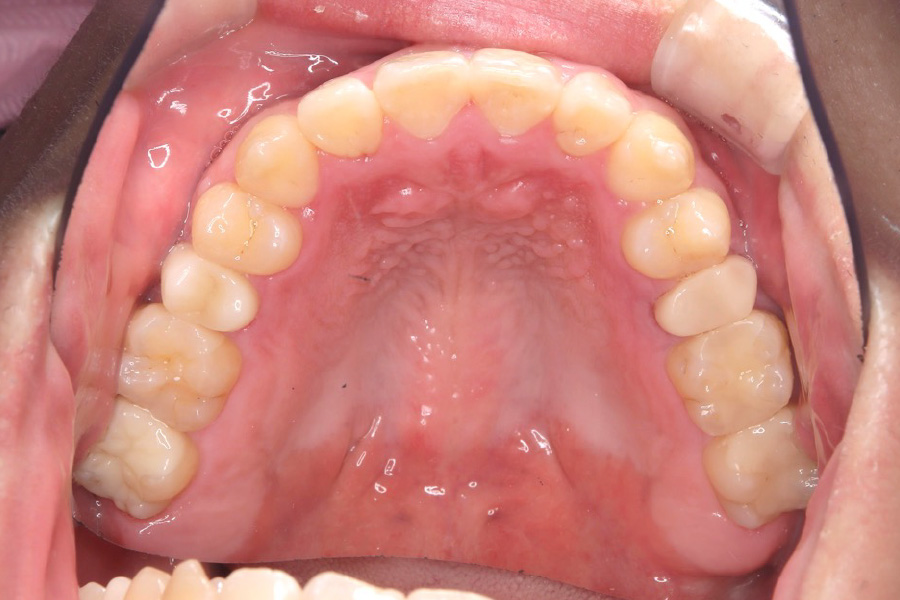

治療前

主訴 歯のガタつき

治療内容 インビザライン矯正

非抜歯